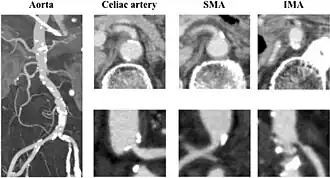

| CT angiogram demonstrating stenosis of the superior mesenteric artery. | |

Abdominal angina is diagnosed by identifying stenosis with imaging.[10] Since the symptoms of abdominal angina overlap with various other disorders, other causes of symptoms are ruled out as a part of the diagnostic process. Gastric ulcers, abdominal aortic aneurysms, and gastrointestinal cancers can have similar symptoms and can be ruled out by esophagogastroduodenoscopy, CT scans, or MR angiogram. Other differential diagnoses include GERD, dietary or food sensitivities, constipation, pancreatitis, abdominal abscess, appendicitis, irritable bowel syndrome, gastroenteritis, hepatitis, and inflammation of the gastrointestinal system.[11] Duplex ultrasound, MR angiography, angiography, and computed tomography angiography can be used to help confirm the diagnosis of abdominal angina.[3] Duplex ultrasound may be used to screen for abdominal angina but is not ideal for visualizing stenosis. Angiography, MR angiography, or CT angiography can be used to further visualize the celiac and mesenteric arteries.[12]